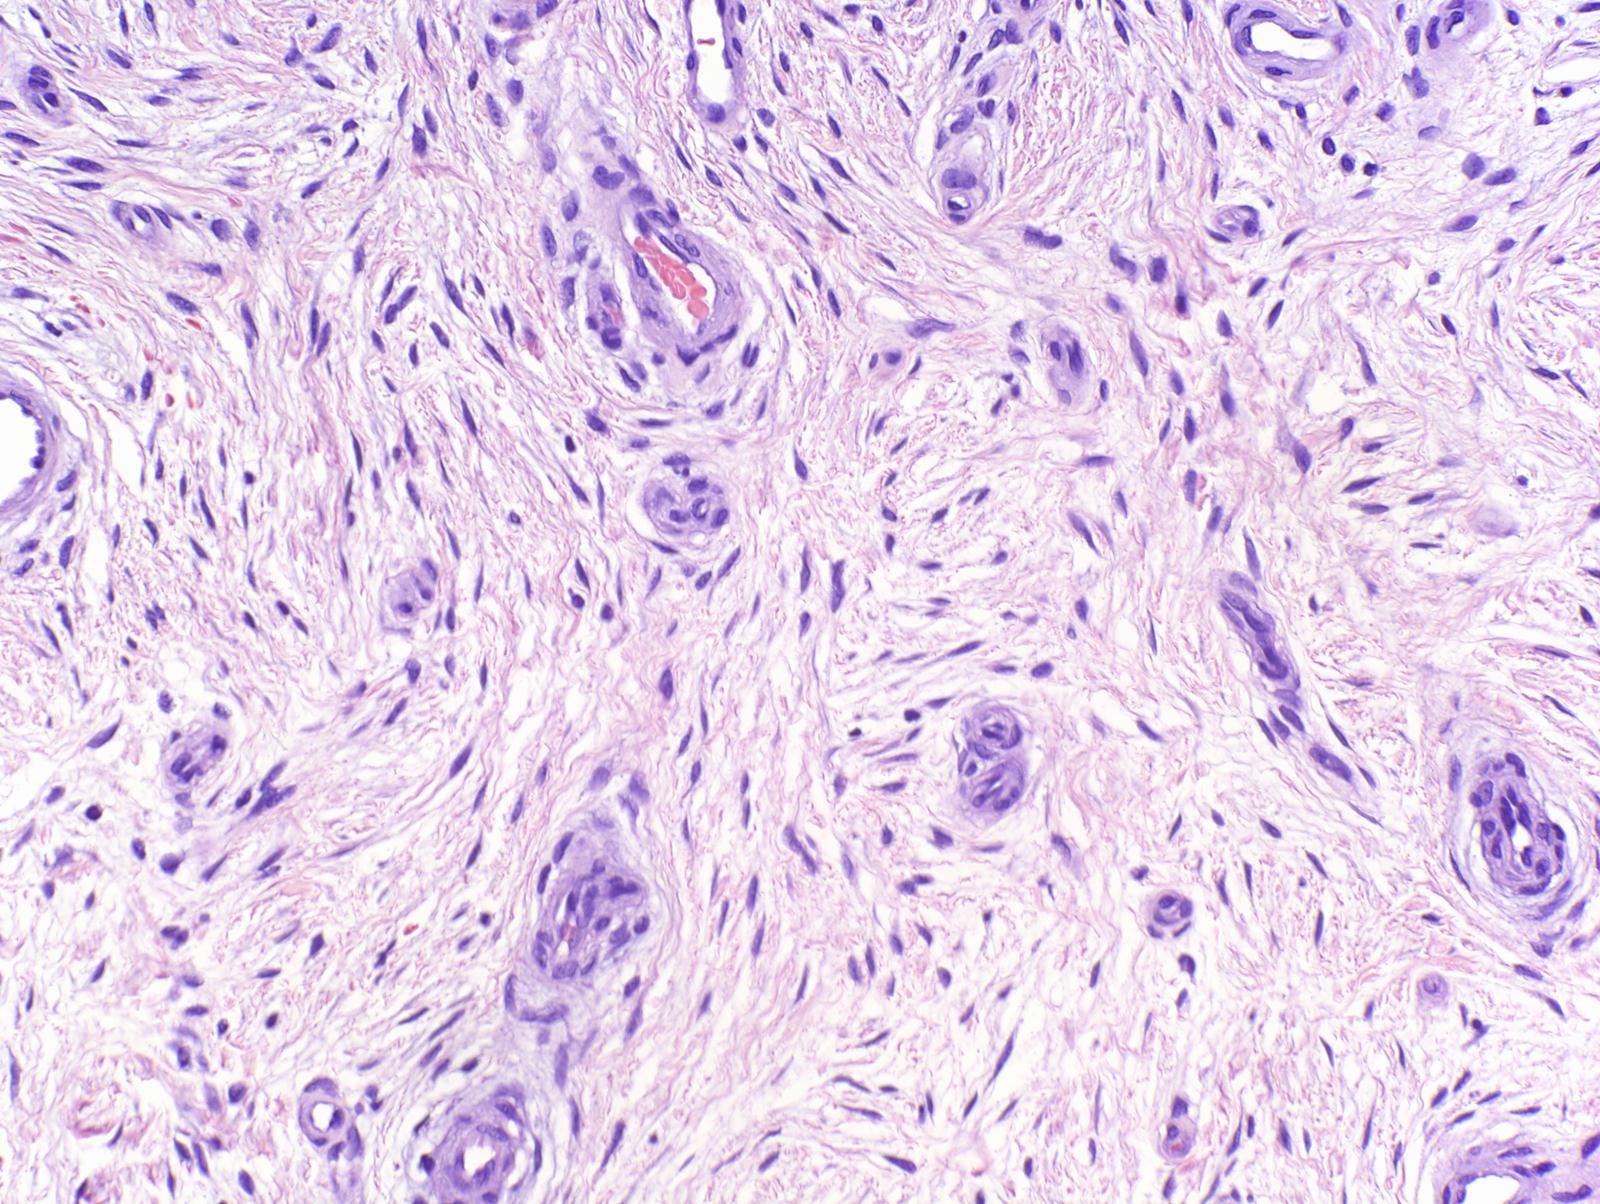

A histologic examination reveals stellate and spindled fibroblast-like cells proliferating moderately within a myxoid and/or collagenous matrix with prominent microvasculature. There may be a hyperkeratotic overlaying epidermis. The tumor cells are distributed in a focally fascicular and loose storiform pattern. This tumor can be positively stained with CD34, CD99, vimentin, and CD10.